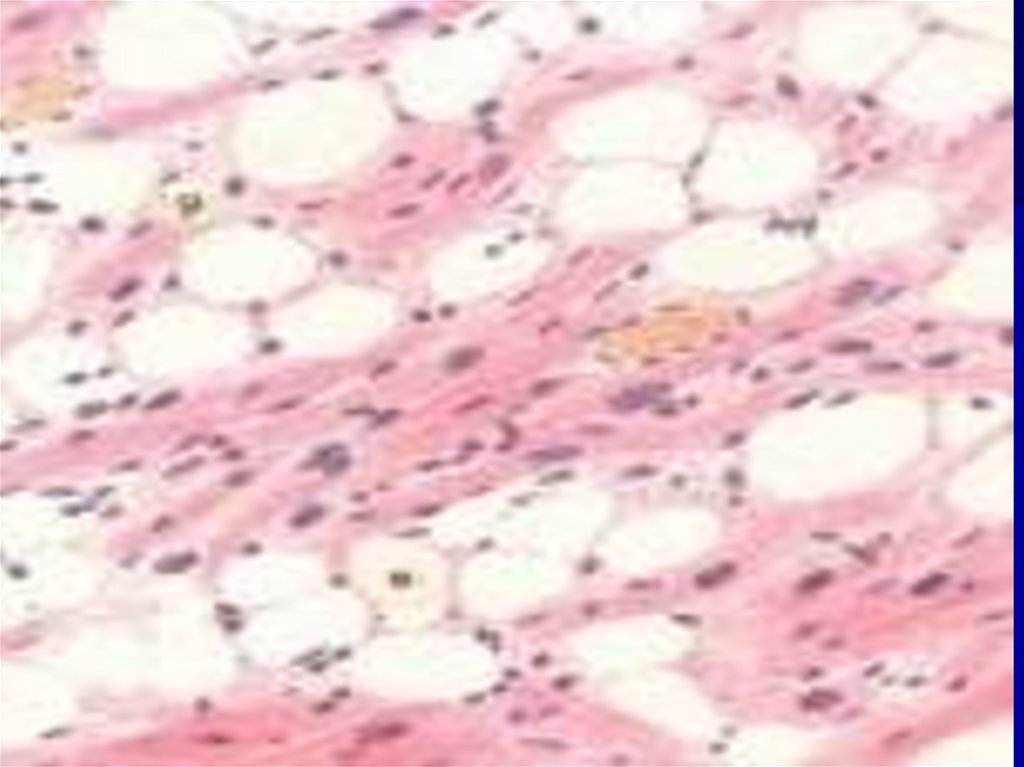

113.

Ожирение сердца

микропрепарат

в стенке правого желудочка пролиферация лейкоцитов в строме, по

ходу сосудов миокарда, атрофия кардиомиоцитов. Окрашивание

гематоксилином и эозином